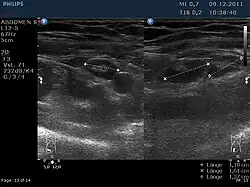

Das klinische Bild ähnelt dem der Appendizitis („Blinddarmentzündung“), die – wie der Morbus Crohn – zu den Differentialdiagnosen der Lymphadenitis mesenterialis gehört. Neben Fieber und Druckschmerz im rechten Unterbauch finden sich oft auch ein auffälliger Befund in der Rektaluntersuchung und eine rektal-axilläre Temperaturdifferenz. Der spezifische Erregernachweis gelingt gelegentlich aus dem Stuhl oder durch Nachweis des Anstiegs der Antikörpertiter. Bei der unspezifischen Lymphadenitis mesenterialis findet sich häufig eine Mitbeteiligung anderer Lymphknotenstationen oder der Tonsillen. Mit hochauflösender Sonografie lassen sich die vergrößerten mesenterialen Lymphknoten oft darstellen.